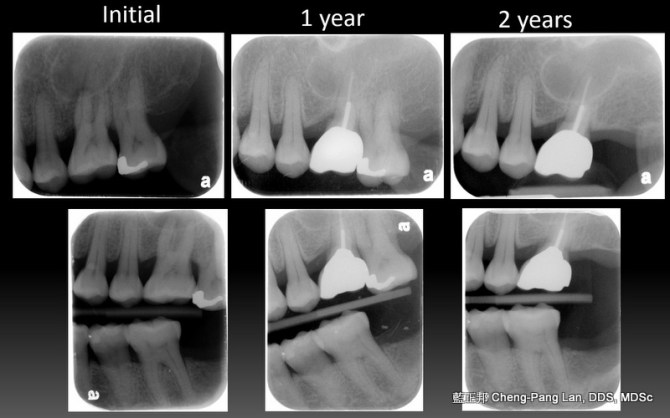

Root Amputation – Case A

This entry was posted in Treatment of Furcation-Involved Teeth and tagged Furcation, Root Amputation. Bookmark the permalink.